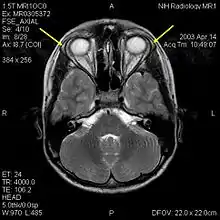

![]() | |

| MRI of the brain of 12-year-old boy with triple-A syndrome showing hypoplastic lacrimal glands (yellow arrows) | |